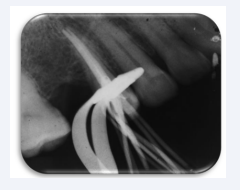

but no pain nor paraesthesia. Radiographically changes were not observed, and root canal treatment was concluded using NaClO 2.5% and biomechanical ProTaper® NiTi rotary instrumentation (Dentsply-Maillefer, Switzerland). For the final procedure, sterile saline solution 0.9% (PiSA®, Mexico) was used for irrigation. Conducts were dried before and after the use of EDTA 17% (Densell, Argentina) during three minutes, and filled and sealed with Hygienic® Gutta Percha points caliber 35 and cement calcium hydroxide-based Sealapex® (SybronEndo, EUA) using a modified ultrasonic side technique (Figure 4).

Obturation radiography; lateral technique with ultrasonic  scale.

Figure 4 Obturation radiography; lateral technique with ultrasonic scale.